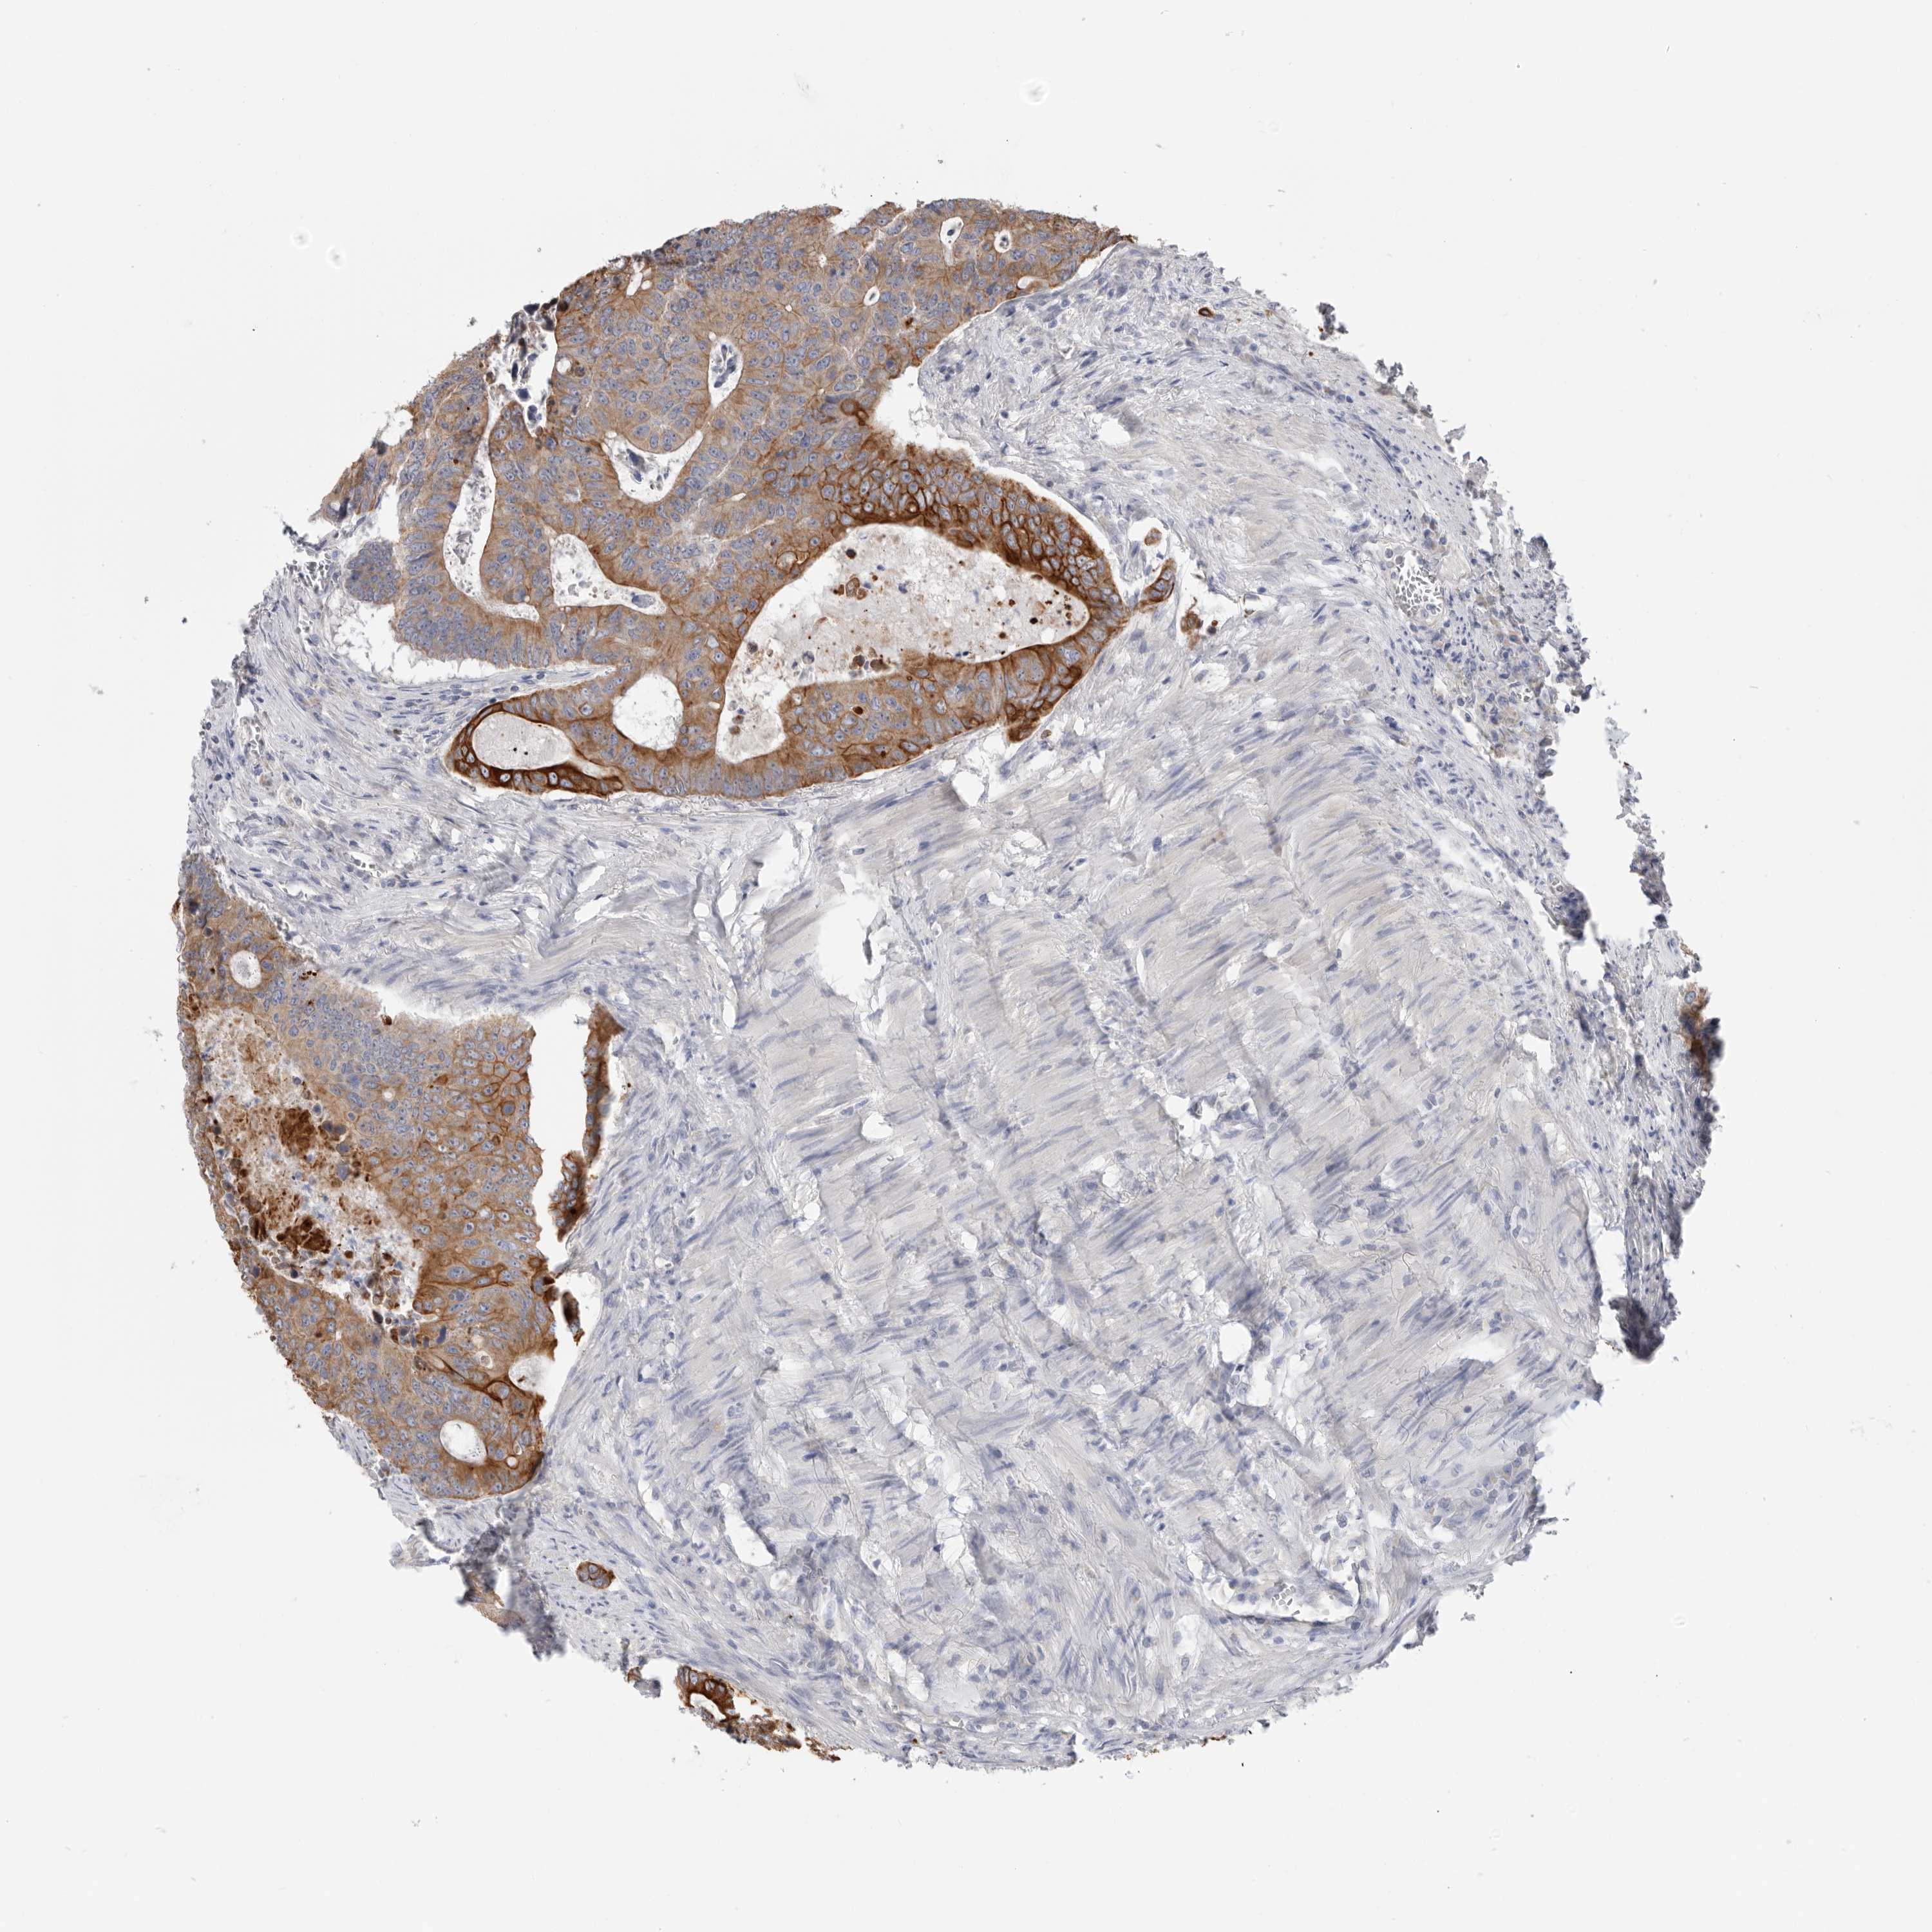

Colorectal cancer

Colon adenocarcinoma